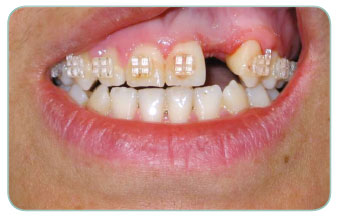

On the back of a trauma our patient had lost his up front teeth. We have applied one Implant together with a zirconium porcelain.